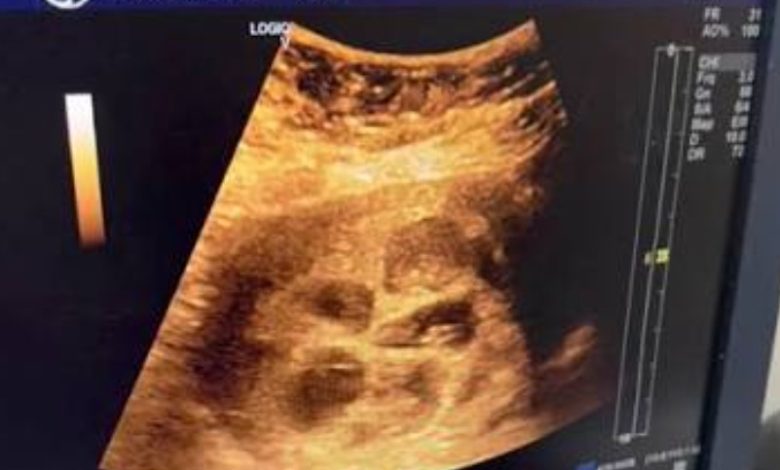

وأظهر مقطع فيديو متداول لحظة قيام طبيب النساء والتوليد بالكشف على السيدة عبر جهاز السونار، حيث تبين وجود ثمانية أجنة داخل الرحم، وهو ما يعد من الحالات النادرة جدًا عالميًا.